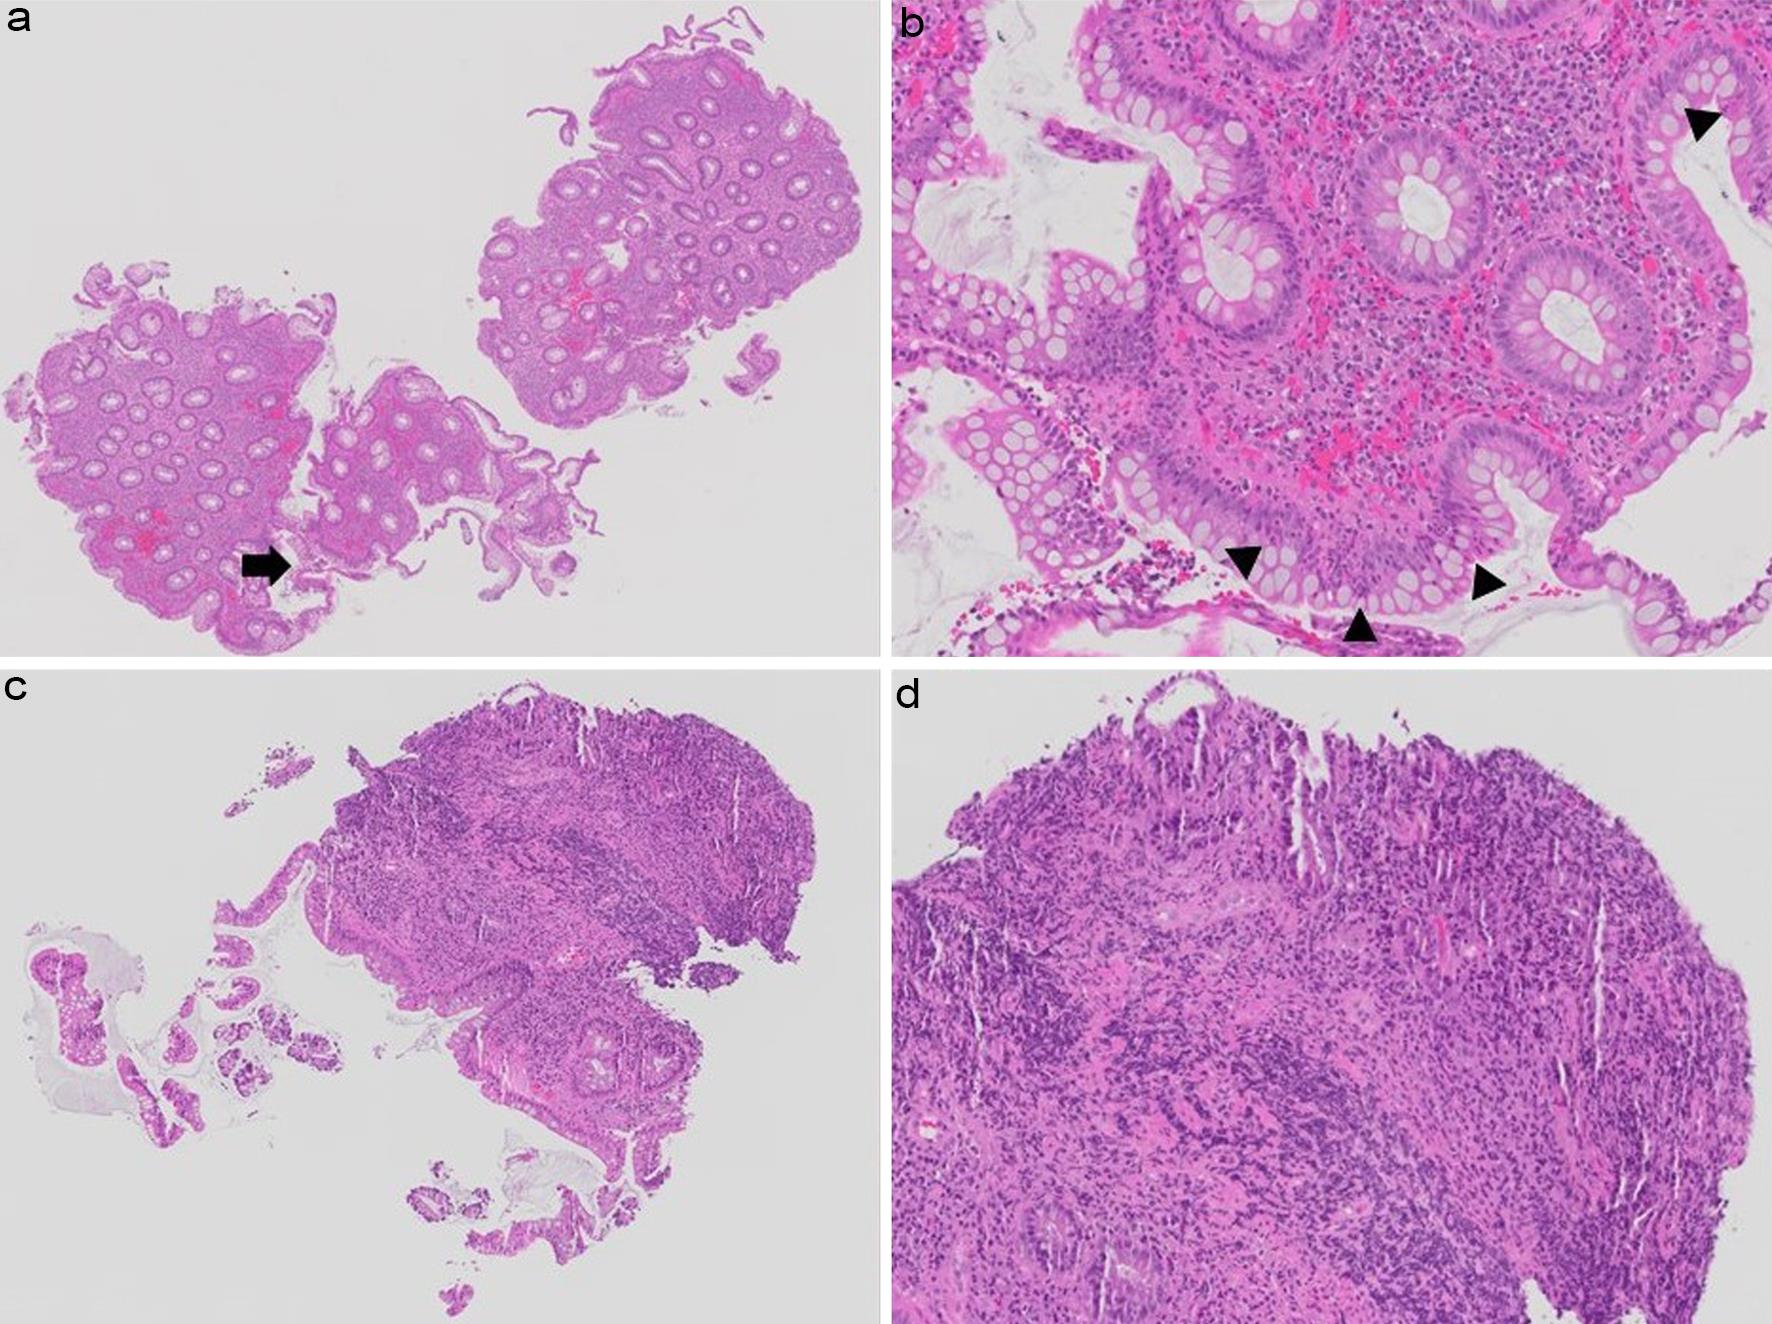

Discrepancy in Nancy index grading of hematoxylin and eosin-stained biopsy images by pathologists.

Fig. 2  Discrepancy in Nancy index grading of hematoxylin and eosin-stained biopsy images by pathologists.

Sigmoid colon biopsy from a patient with treated ulcerative colitis showing chronic inflammation in the lamina propria and a focal area (black arrow in a) with intraepithelial and lamina propria neutrophils (arrowheads in b). At the first review, 8/12 pathologists assigned Grade 2, 3/12 assigned Grade 3, and 1/12 assigned Grade 1. At the second review, 7/12 pathologists assigned Grade 2, and 5/12 assigned Grade 3. Of note, 11/12 pathologists at review 1 and 12/12 at review 2 indicated that this biopsy had active disease. Rectal biopsy from a patient with treated ulcerative colitis showing chronic inflammatory infiltrate in the lamina propria (c) and a possible ulceration with granulation tissue-like appearance (d). At the first review, 7/12 pathologists assigned Grade 4, 4/12 assigned Grade 1, and 1/12 assigned Grade 2. At the second review, 7/12 pathologists assigned Grade 4, 2/12 assigned Grade 2, and Grades 0, 1, and 3 were each assigned by 1/12 pathologists. Notably, 9/12 pathologists at review 1 and 10/12 at review 2 indicated that this biopsy had active disease. (Hematoxylin-eosin stain; original magnifications: 3.2× in a, 20× in b, 4× in c, and 20× in d).